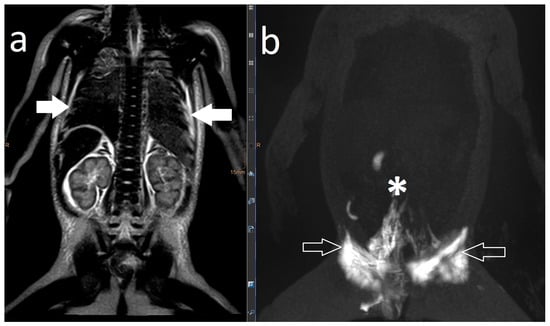

| 21 | 4 | increased signal mediastinum, hilum, lung le > ri | retrograde flow from TD with diffuse mediastinal and peribronchial perfusion | thoracic vertebrae 4–10 to left mediastinum | MCT diet, macitentan, alteplase inhalation, salbutamol, diuretics | glue embolization of TD | cast free after intervention (FU 1 a 4 m) tapering off sildenafil |

| 22 | 4 | increased signal (mediastinum), hilum/lung ri | retrograde lymphatic flow to mediastinum and lung parenchyma ri | from hilum to ri lung | fat reduced diet, sildenafil, alteplase/ fluticasone inhalation | selective glue embolization of 2 branches of TD | cast free after intervention (FU 4 a), cessation of fat-reduced diet, |

| 23 | 4 | increased signal mediastinum, hilum, lung ri > le | retrograde lymphatic flow towards lung parenchyma & mediastinum ri > le and peribronchial perfusion | fistula visualized | fat reduced diet, sildenafil, diuretics, alteplase inhalation, azithromycine | selective glue embolization of fistulas | cast free after intervention (FU 1 a 4 m) |

| 24 | 4 | increased signal at the mediastinum and hilum bilateral | retrograde lymphatic flow towards mediastinum and hilum bilaterally | no fistula visualized | diuretics salbutamol inhalation. Budesonide | TD decompression | cast free after OP, albumin normalized (FU 3 a 5 m) |

| 25 | 4 | increased signal neck, axilla, mediastinum, hilum, lung ri, fistula from liver to ri lung | little contrast | no fistula visualized | lisinopril, diuretics, spironolactone, bisoprolol, sildenafil, diuretics, alteplase inhalation. | not performed yet | still casts |

| 26 | 4 | increased signal neck, axilla, mediastinum, hilum, lung | retrograde lymphatic flow towards mediastinum, hilum and lung parenchyma with peribronchial perfusion ri | from hilum to ri lung | spironolactone, sildenafil, diuretics, alteplase inhalation, hydrochlorothiazide | not performed yet | still casts |